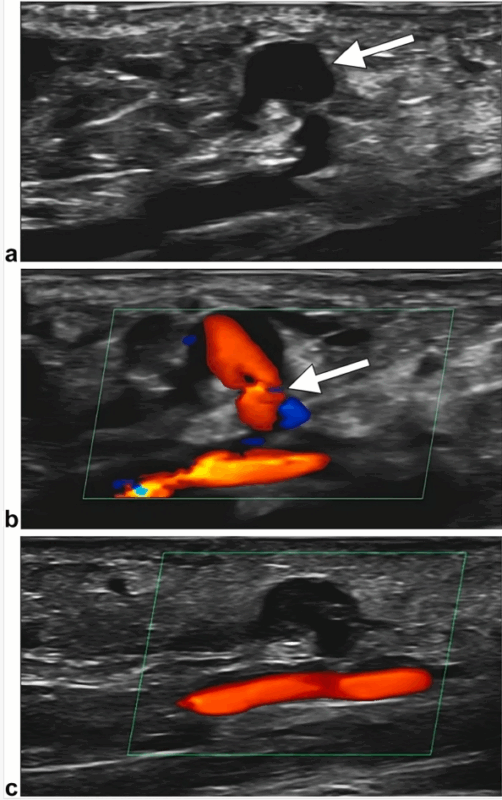

The day after successful rental artery stenting via left transradial access, our patient developed a pulsatile mass at the puncture site. Doppler US showed a 9 × 7–mm saccular outpouching of the superficial radial artery wall (arrow, Fig 1a) with turbulent flow through a narrow 2-mm neck (arrow, Fig 1b), consistent with pseudoaneurysm. To attempt non-invasive management, the skin overlying the lesion was marked under US guidance. A TR Band was applied directly over the pseudoaneurysm and inflated with 12 mL of air (nonocclusively) for 48 hours, allowing sufficient time for immobilization and spontaneous thrombosis. Follow-up Doppler US confirmed complete thrombosis with patent parent artery (Fig 1c). Recovery was uneventful.